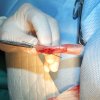

Velmi komplikovaná fraktura obou předloketních kostí u drobné činčily, jelikož se tak drobné implatáty běžně nevyrábějí, řešili jsme ji implantací nitrodřeňových hřebů vyrobených z injekčních jehel. Pacient se kompletně a bez následků uzdravil, po vyjmutí hřebů nožičku naplno používá.